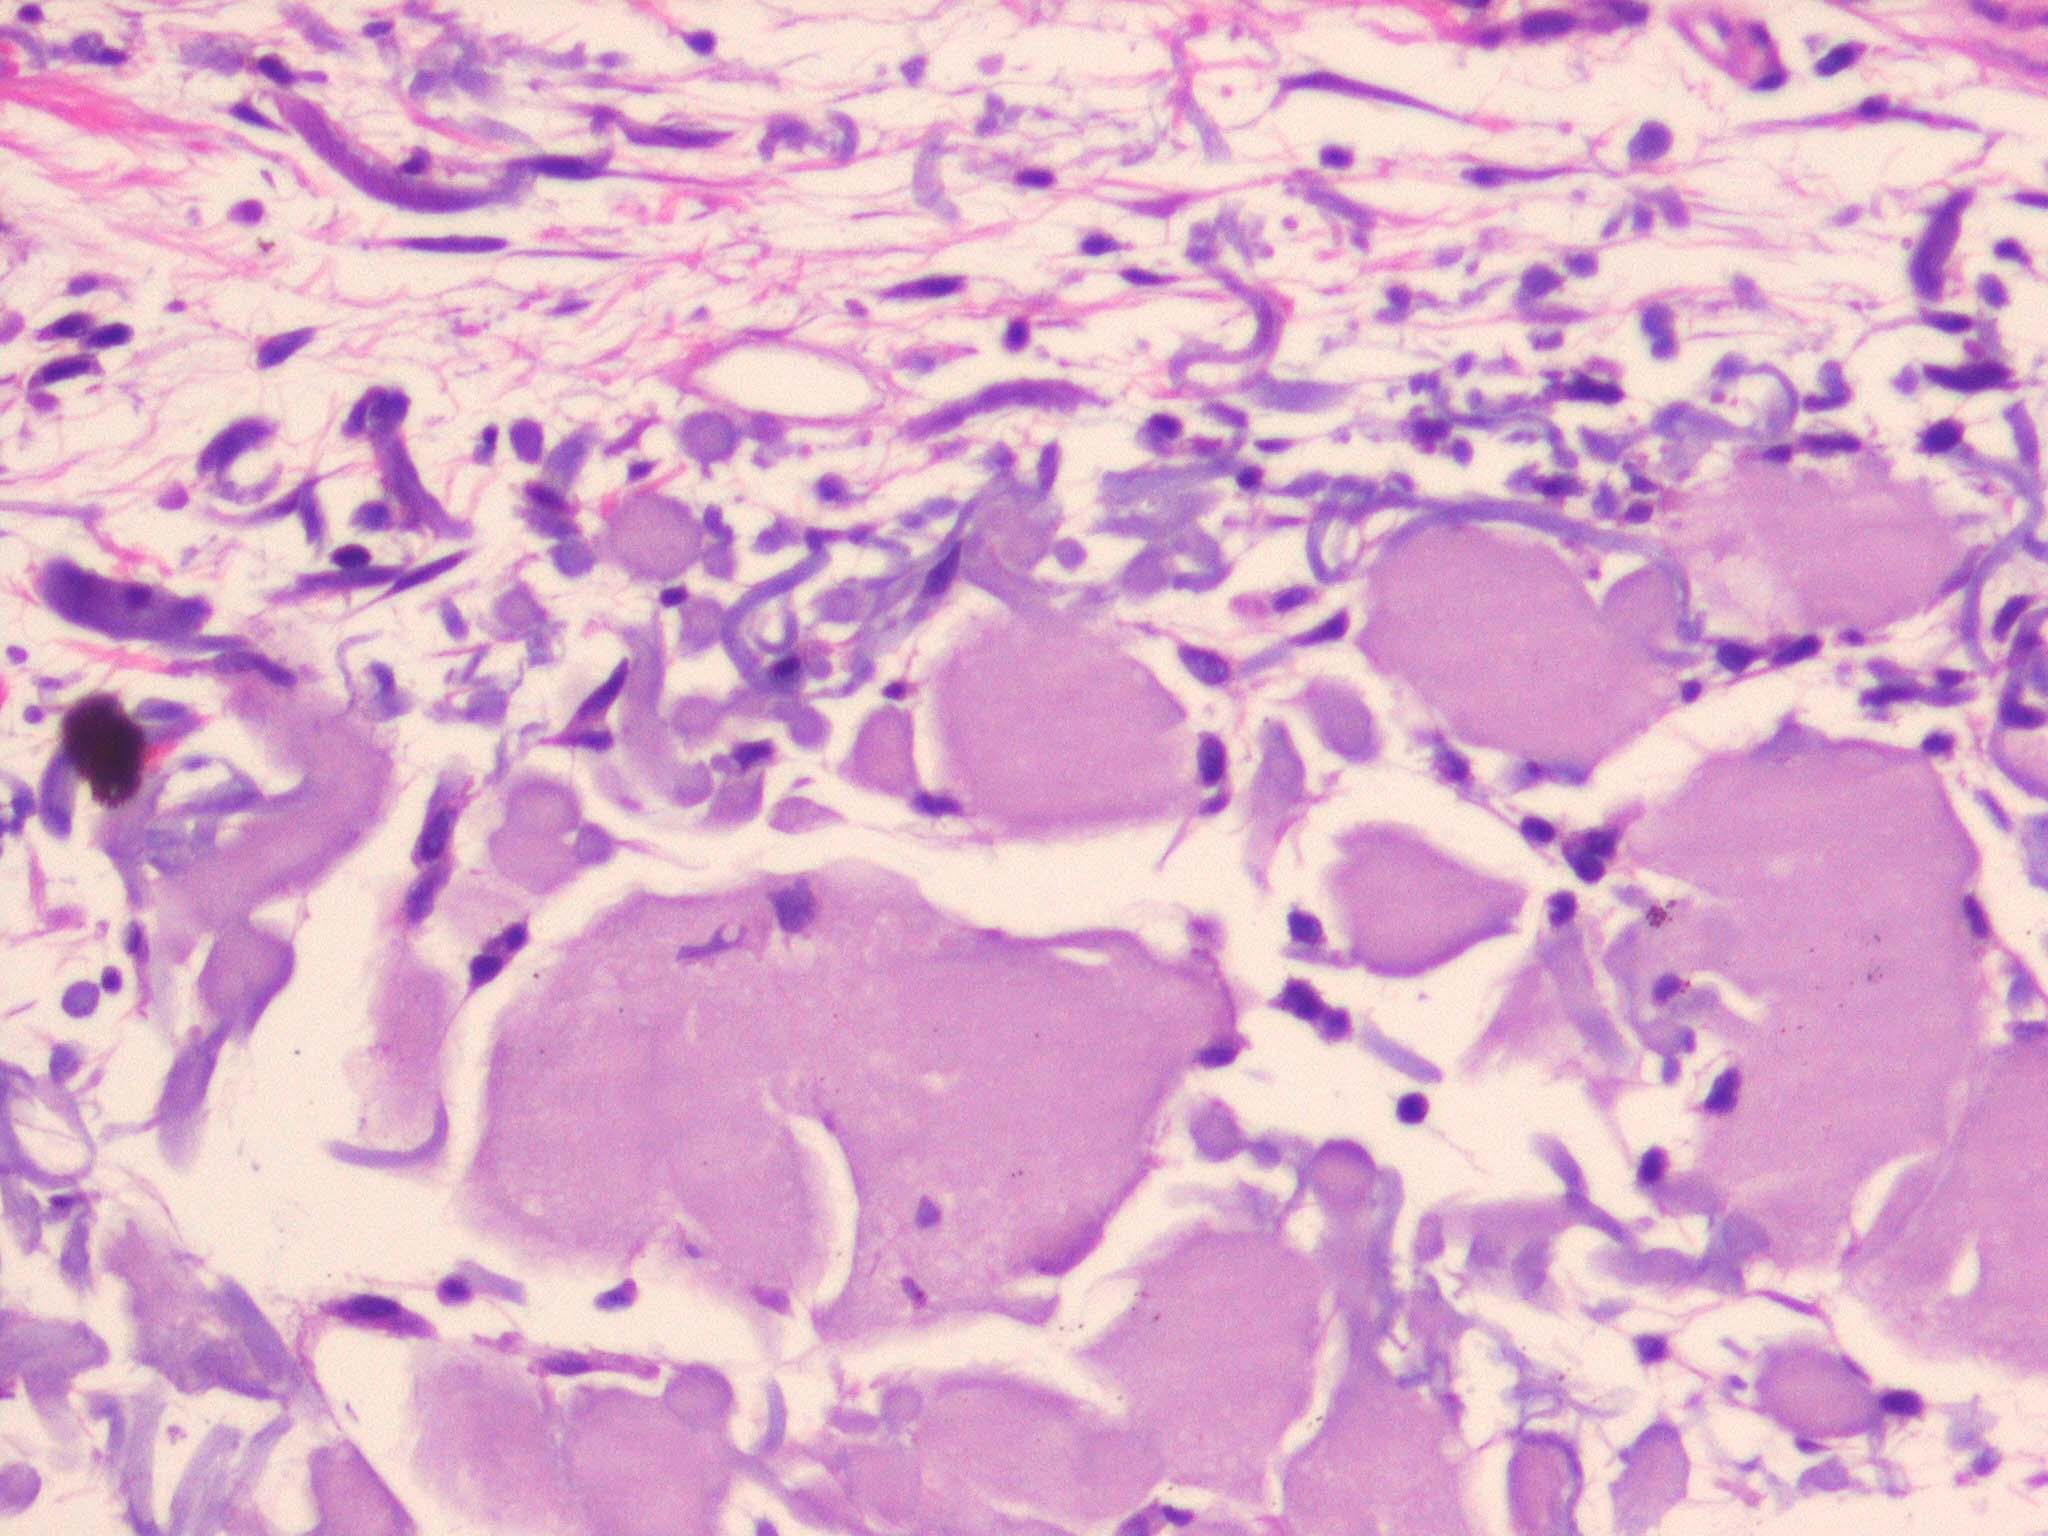

Colloid milium is a rare condition characterized by (1) the presence of multiple, dome-shaped, amber- or flesh-colored papules developing on light-exposed skin and (2) the observance of dermal colloid under light microscopy. The 4 variants are (1) an adult-onset type, (2) a nodular form (nodular colloid degeneration),1 (3) a juvenile form,2,3 and (4) a pigmented form, thought to be due to excess hydroquinone use for skin bleaching.4

• Skin lesions of colloid milium: Amber, waxy, partially translucent, firm papules occur in crops, ranging from 1-5 mm in diameter. Gelatinous material can be expressed. In the nodular form, larger nodules (5-10 mm) or plaques develop. The underlying skin may be thickened, furrowed, and hyperpigmented. In the pigmented form, the papules are gray-black and confluent or clustered.